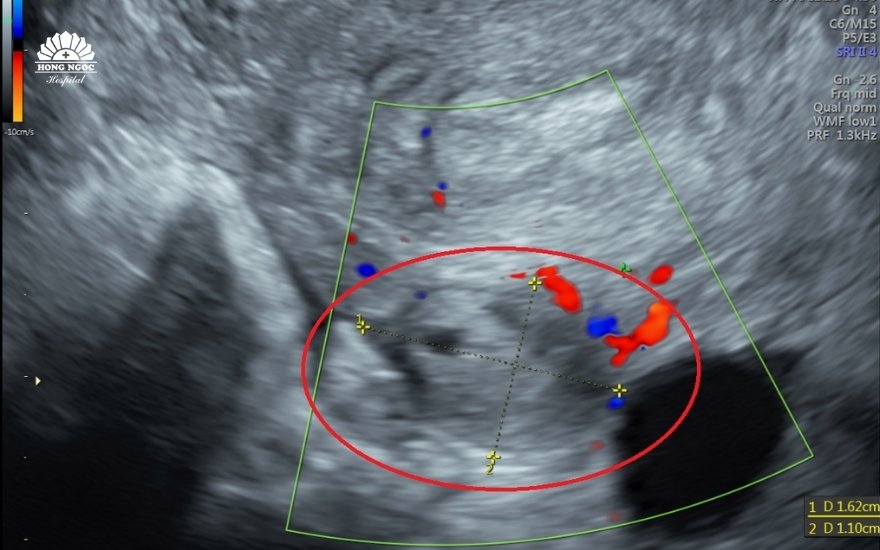

BSCKII Đỗ Văn Tú, Trưởng khoa Sản Phụ khoa - BVĐK Hồng Ngọc Yên Ninh chia sẻ: "Khi siêu âm, chúng tôi không phát hiện thấy phôi thai trong tử cung, mặc dù chị L thử thai tại nhà cho kết quả hai vạch . Thay vào đó, một khối kích thước 10x13mm ở vị trí buồng trứng trái khiến chúng tôi nghi ngờ là thai ngoài tử cung và có thể cần thuật thuật để bảo vệ tính mạng cho mẹ."

Hình ảnh siêu âm cho thấy tại buồng trứng trái có khối KT: 11x15mm nghi ngờ thai ngoài tử cung